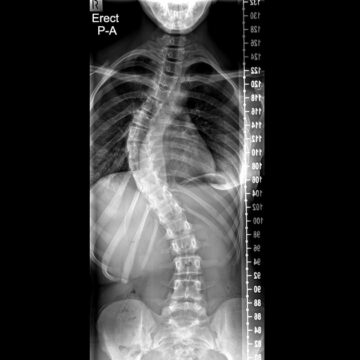

اعوجاج العمود الفقري : الأسباب، الأعراض، التشخيص والعلاج اعوجاج العمود الفقري هو انحناء جانبي غير طبيعي في العمود الفقري، بحيث يظهر العمود الفقري بشكل حرف (S) أو حرف (C) بدلًا من أن يكون مستقيمًا

اعوجاج العمود الفقري عند الأطفال | الأسباب، الأعراض، وطرق العلاج المبكر يُعد اعوجاج العمود الفقري (الجنف) من أكثر مشكلات العمود الفقري شيوعًا عند الأطفال والمراهقين. تشير الدراسات إلى أنه يصيب ما يقارب 3% من

اعوجاج العمود الفقري مجهول السبب عند المراهقين: دليلك للاكتشاف المبكر والعلاج الفعّال اعوجاج العمود الفقري مجهول السبب، المعروف طبيًا باسم الجنف مجهول السبب، هو انحناء جانبي غير طبيعي للعمود الفقري يظهر غالبًا خلال مرحلة